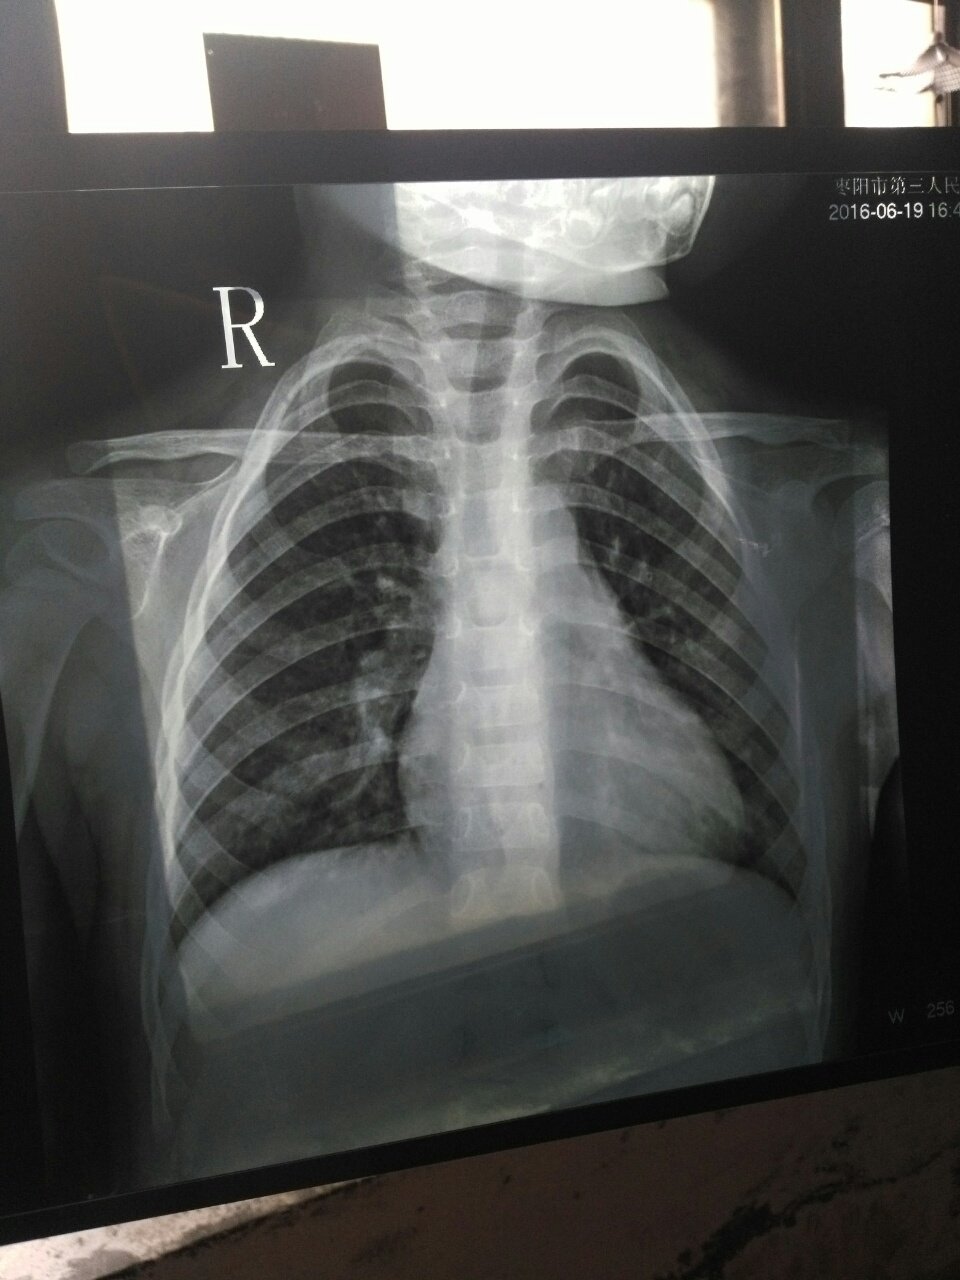

刚刚在医院給娃拍的肺部片子,医生帮我看看是不是肺炎 刚刚在医院給娃拍的肺部片子,医生帮我看看是不是肺炎 点击展开 181*****776_VM7o 2016-06-19 18:14 为您推荐: 其他回答 ,,,,,, 可忆 2016-06-19 18:16 相关问题 请问小孩子肺部拍片子说一点问题都没有,医生却说是肺炎 我老婆不知道怀孕,在怀孕两周去医院照了胸和肺部的片子医生说肺部有点炎症吃了三付中药现在六周了请问对 新生儿十一天,照片支肺炎,不过没有流鼻涕、咳嗽、呕吐、发烧等症状,片子肺部有一点点杂点,可能是X